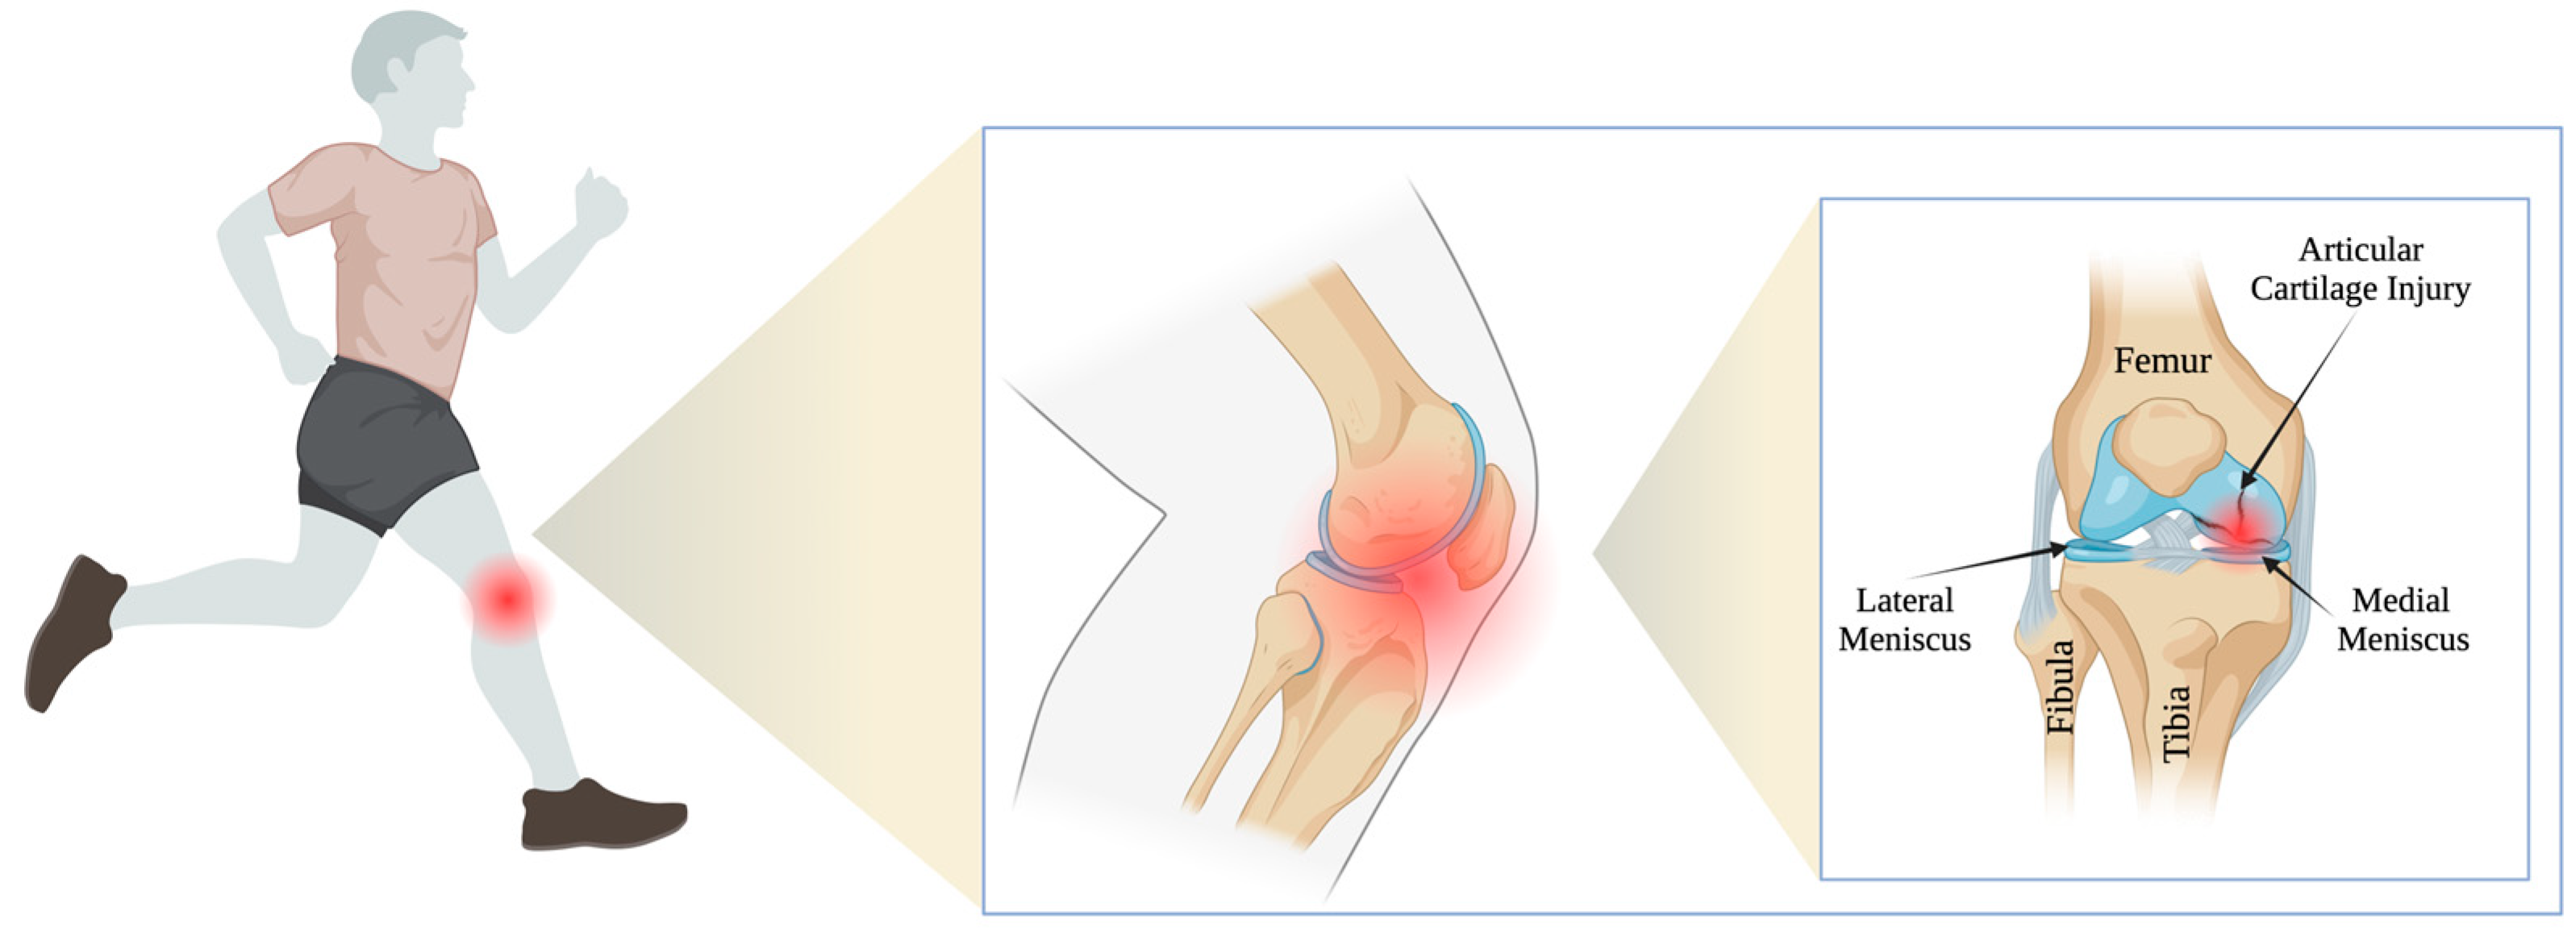

The treatment of articular cartilage injuries has been a challenge for doctors around the world for decades. This is due to the fact that articular cartilage has limited healing potential due to a lack of blood vessels and nerve connections. Tissue nutrition depends mainly on the diffusion of nutrients from the joint cavity [1,2,3,4]. Articular cartilage damage is typically a long-term clinical orthopedic issue that has a huge impact on the functionality of people at any age [5,6]. The problem is so widespread that it currently affects more than 50 million American adults, and it is estimated that this number is expected to rise to approximately 67 million by 2030 [5,7]. Intra-articular injuries, potentially leading to degenerative changes, are much more common in the case of professional athletes [8]. Epidemiological data suggest that athletes suffering from acute injuries and experiencing long-term stress on their joints related to rapid turns and changes of direction reveal symptoms of cartilage damage and early degenerative changes more frequently [9,10] (Figure 1). Physical activity through participation in organized team sports plays an important role in maintaining joint cartilage health. At the same time, it is also beneficial in limiting the progression of osteoarthritis (OA) [11,12,13]. However, participation in some sports may increase the risk of knee OA, which has been reported in contact and collision sports (e.g., soccer [14,15,16] and rugby [17]).

Figure 1.

Articular cartilage injury in athletes.